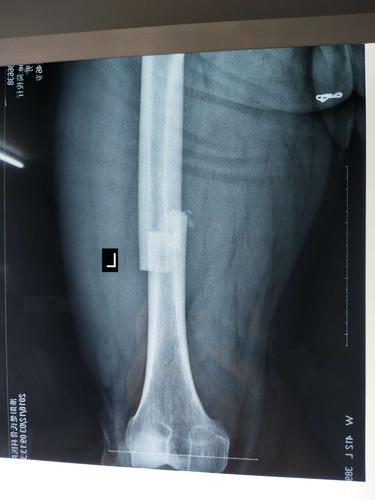

其它 刘威的美篇 写美篇贺**,女,左股骨干中段骨折,行股骨干骨折闭合

逆行髓内钉治疗双侧股骨干骨折

股骨干骨折闭合复位髓内固定

左股骨干骨折骨痂图片